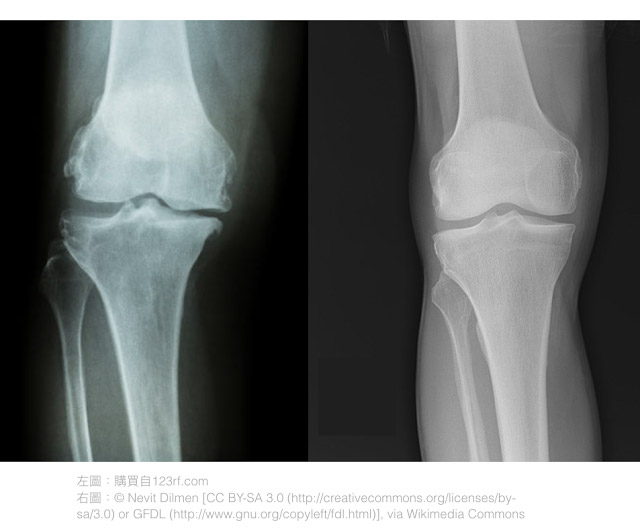

上面右圖是正常的膝關節,可以看到骨頭與骨頭之間有充足的空間,這層空間由軟骨所佔據。而左圖的膝關節內側的空間明顯變窄了,這意味著軟骨的厚度降低(註2)